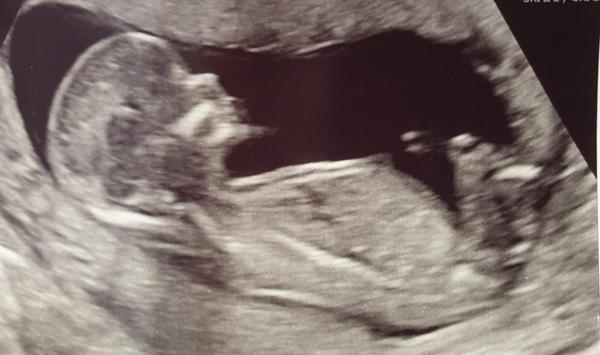

We had our scan this morning and baby was perfect the sonographer even said it was the best scan she's done in terms of clarity and getting the measurements! 13+5 so due date 15th September.

Hope everyone else is keeping well and good luck to all those with scans still to come.

I thought boy from my symptoms but the nub shot on our scan picture made me think girlie — quite interesting the nub theory!

Congratulations Bridget! Can you see the nub on your picture above? I don't think you can see it on mine, because of the leg placement, but yours looks very similar. I'm not finding out, but that's not going to stop me guessing!